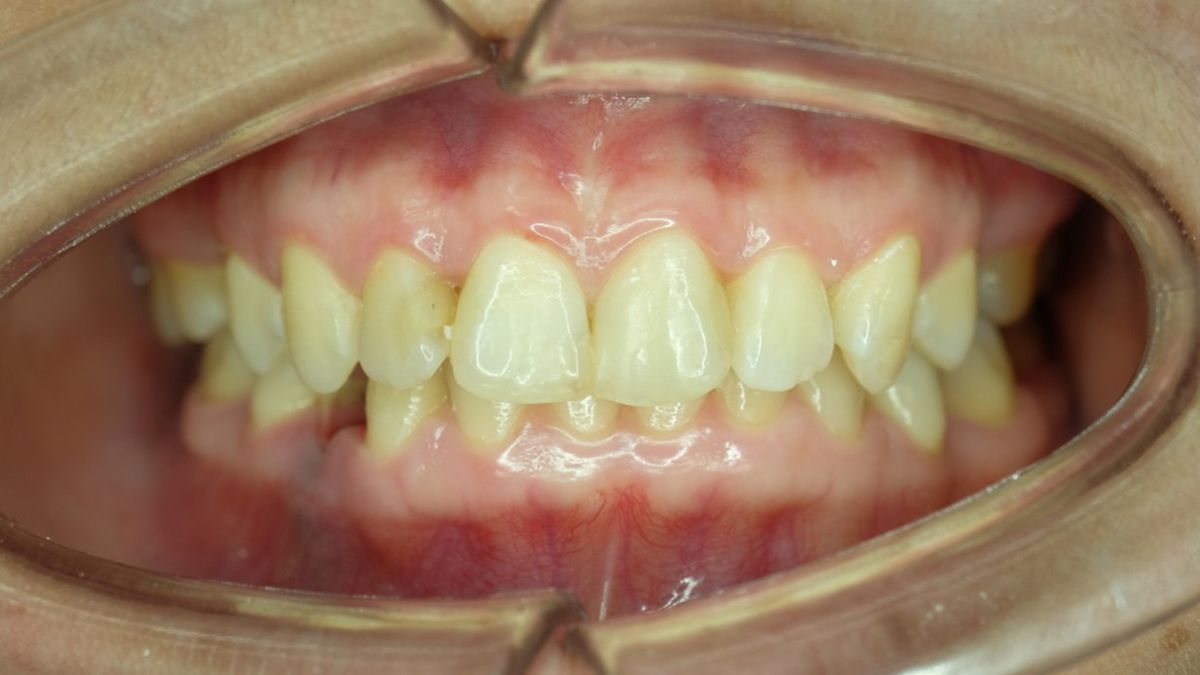

Zgryz głęboki to wada zgryzu, istotą której jest nadmierne nachodzenie przednich zębów górnych na zęby dolne. W wyniku tej nieprawidłowości, zęby dolne są przykryte co najmniej w 2/3 przez zęby górne. Zazwyczaj obserwuje się cofnięcie się dolnej szczęki, a wysunięcie się szczęki górnej. W przebiegu zaburzenia stwierdza się zatem zwiększony nagryz pionowy.

Ten rodzaj wady zgryzu nie ma dużego wpływu na estetykę wyglądu, choć twarz może mieć lekko kwadratowy kształt. Zdarza się też, że zgryz głęboki skutkuje „wypukłymi zębami” i tzw. uciekającą brodą. Objawem zgryzu głębokiego może być także większe napięcie warg oraz częste ścieranie się szkliwa po wewnętrznej stronie górnych siekaczy oraz po zewnętrznej stronie siekaczy dolnych. Wiele zależy od stopnia zaawansowania nieprawidłowości.

• zgryz głęboki częściowy, czyli wydłużenie się górnych siekaczy tak, że przykrywają siekacze dolne. Określany jest on jako nadgryz, który w efekcie nieprawidłowego wzrostu wyrostka zębodołowego cechuje nadmiernie zwiększona podstawa korzeniowa siekaczy szczęki,

• zgryz głęboki całkowity, czyli skrócenie szczęki oraz wywinięcie dolnej wargi, czemu może towarzyszyć pogłębienie się bruzdy wargowo-bródkowej. Ten rodzaj wady objawia się bardzo nasilonym nagryzem w odcinku przednim i wywołuje zmiany w estetyce twarzy: prowadzi do skrócenia jej dolnego odcinka oraz wywinięcia warg,